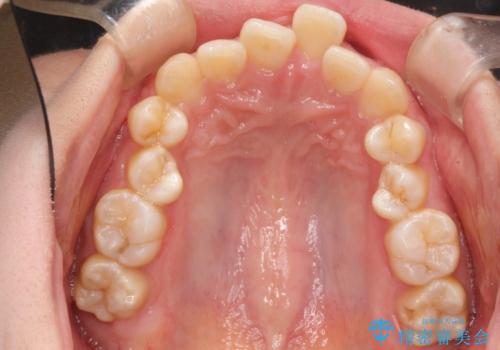

重度のガタガタのインビザラインによる非抜歯矯正

- 全体的なガタガタを気にされて来院されました。

抜歯矯正も考えられる状態でしたが、ご本人的になるべく歯を抜かない矯正を希望されました。

奥歯を後方に移動させるのと、歯と歯の間にわずかに隙間を作ることでスペースを確保して、抜歯をせず歯を並べる計画としました。

ガタガタの度合いが大きかったので少し時間がかかりましたが、非常に協力的な患者様でしたので、抜歯をせず計画通りに治療を終えることができました。